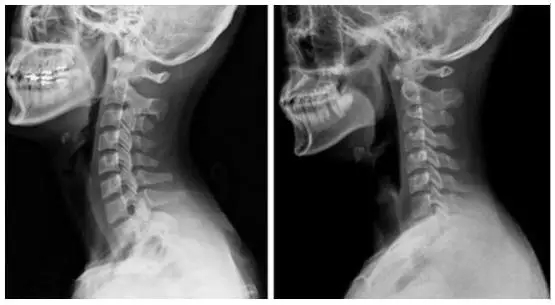

正常情况下,人的颈部呈现一定的弧度,具体表现为向前凸起,如下图左。但是由于一些外因作用,如长期低头伏案工作、埋头玩手机等,造成颈椎过度前屈,从而造成颈椎生理曲度变直,如下图右。

枕头过高也是导致这种颈椎生理曲度变化的外因之一。枕头过高,颈部呈过度屈曲状态,时间久了,会导致颈部周围的韧带受牵拉损伤,最后变得松弛,进一步颈椎的稳定性会减退,造成脊柱失稳。枕头过矮,容易出现打呼噜、落枕的现象,会加重骨质增生。